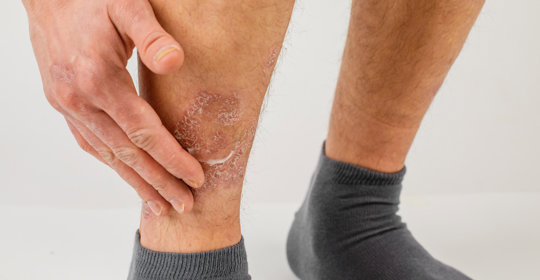

臨床上測量靜脈曲張的方法主要包括體格檢查、血常規檢查等。如果患者存在下肢靜脈曲張的情況,則建議及時到醫院的血管外科就診,在醫生指導下進行治療。